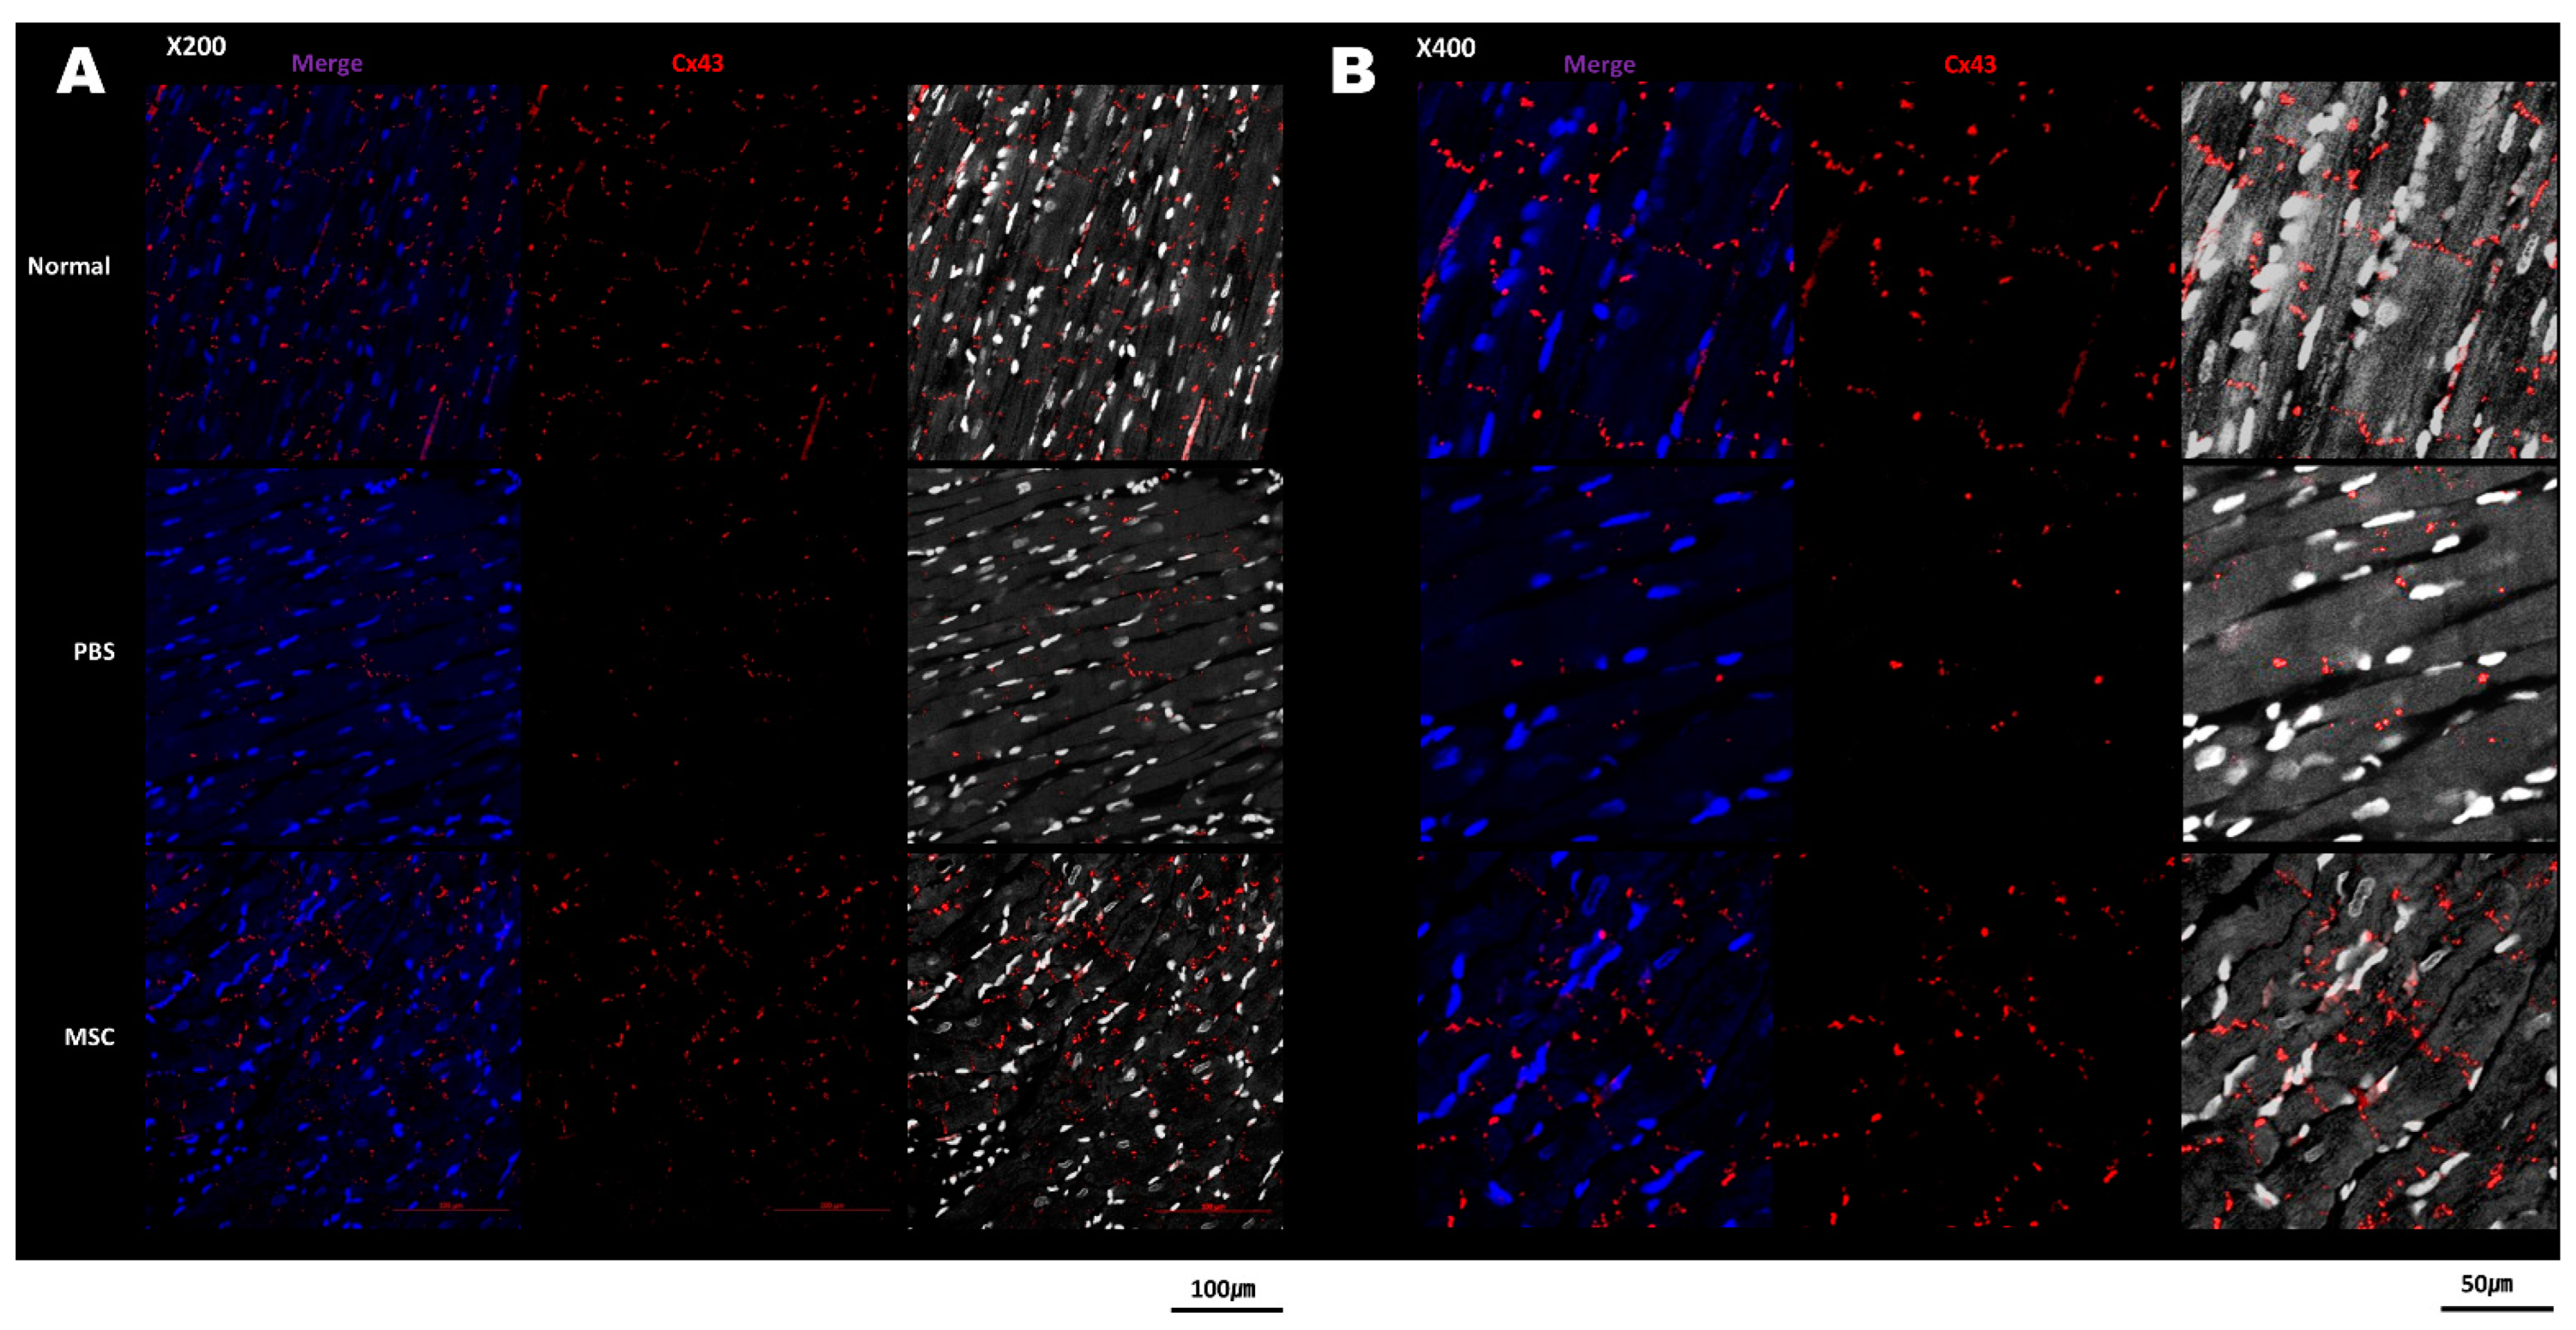

3.3. Histology and Cx43 Expression